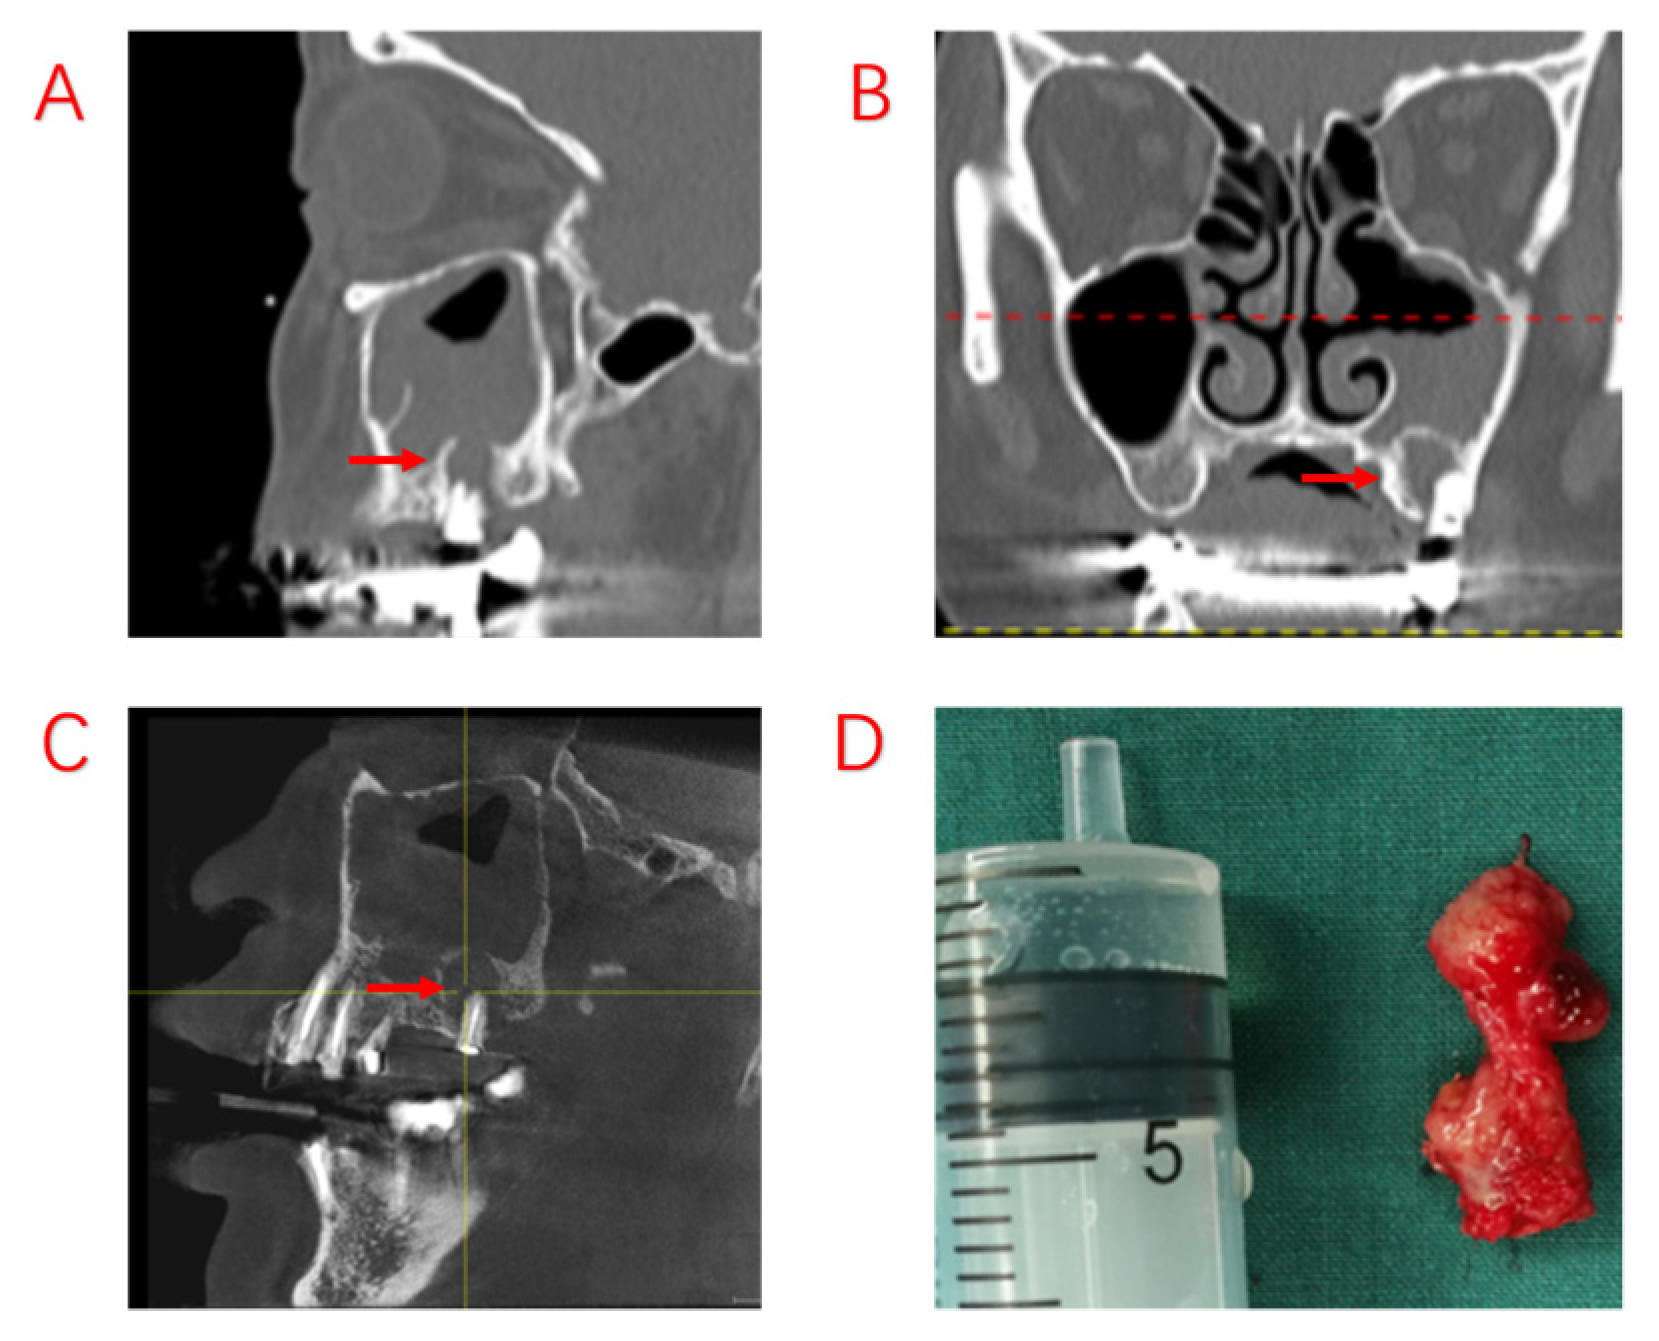

Figure 3.

Recurrence of postoperative sinus symptoms after ESS for odontogenic sinusitis due to failure to treat the apical lesion. (A,B): Large shading of the apical area of the diseased tooth and bone penetration of the maxillary sinus floor. The maxillary sinus opening was fully opened after ESS, and the maxillary sinus mucosa could not heal completely due to the apical lesion not having been removed. (C): The apical lesion persisted despite RCT of the diseased tooth. (D): A large amount of diseased granulation tissue adhered to the apical lesion. Red arrows indicate sites of apical inflammation.